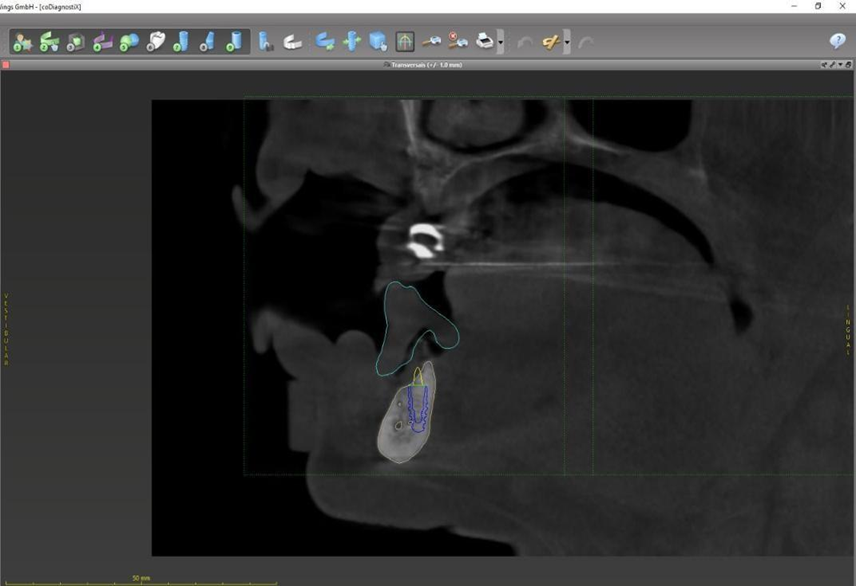

Paciente de 62 anos, do sexo feminino, sem comorbidades e história médica pregressa, apresentava severa reabsorção óssea em regiões anteriores e posteriores da mandíbula devido a uma peri-implantite (Figuras 1A e 1B). Feita a remoção dos implantes, a paciente optou por utilizar uma prótese total mucossuportada até a nova intervenção com prótese do tipo protocolo inferior. Após seis meses, a mandíbula encontrava-se cicatrizada (Figura 2). Como parte do protocolo diagnóstico, foi realizada tomografia computadorizada pela técnica do duplo DICOM. Com a severa perda óssea em região anterior de mandíbula, optamos por realizar a cirurgia de forma guiada, aumentando a previsibilidade e precisão da cirurgia. Os arquivos obtidos foram exportados para o software CoDiagnostiX, possibilitando a realização do planejamento reverso e o subsequente posicionamento virtual dos implantes (Figura 3). Com base no planejamento, optou-se pela instalação de quatro implantes Implacil Osstem CM AR Due Cone (3,5 x 7 mm), associados a mini-cônicos de 1,5 mm (Figuras 4A, 4B, 4C, 4D e 4E). A partir da tomografia da prótese da própria paciente, confeccionaram-se duas guias cirúrgicas: uma guia de pino de fixação (Figura 5) e uma guia de fresagem para a instalação dos implantes (Figura 6). Durante o procedimento cirúrgico, inicialmente foi posicionada a guia de pino de fixação para fresagem dos pinos de fixação e orientação da sequência cirúrgica (Figura 7). Após essa etapa, a guia foi substituída pela guia de fresagem dos implantes (Figura 8), utilizada para a fresagem e inserção dos implantes planejados (Figura 9). Concluída a instalação, optou-se por seguir o fluxo analógico, com a adaptação dos mini-cônicos 1.5 mm (Figura 10), realização da transferência de moldagem com silicona de adição leve e sutura com fio absorvível Vycril 6-0. O guia inicial foi adaptado com broca Maxicut, possibilitando sua utilização como molde de orientação para o laboratório protético (Figura 11). Após a moldagem, foram posicionadas as tampas de proteção sobre os implantes. Na fase protética, transcorridas 48 horas do procedimento cirúrgico, foi realizada a prova clínica da barra metálica e dos dentes (Figura 12). Na etapa subsequente, 72 horas após a cirurgia, procedeu-se à instalação e entrega do protocolo mandibular inferior e radiografia prévia, reabilitando funcional e esteticamente a paciente em curto espaço de tempo (Figuras 13A e 13B).